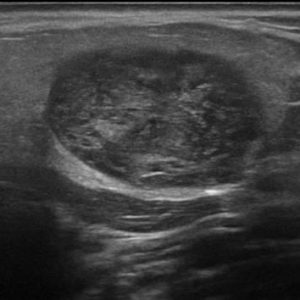

U tuyến nước bọt

Lượt xem: 138» 19-01-2021 -

U tuyến nước bọt

Lượt xem: 153» 19-01-2021 -

U tuyến nước bọt

Lượt xem: 131» 19-01-2021 -

U tuyến nước bọt

Lượt xem: 102» 19-01-2021 -

U tuyến nước bọt

Lượt xem: 146» 19-01-2021 -